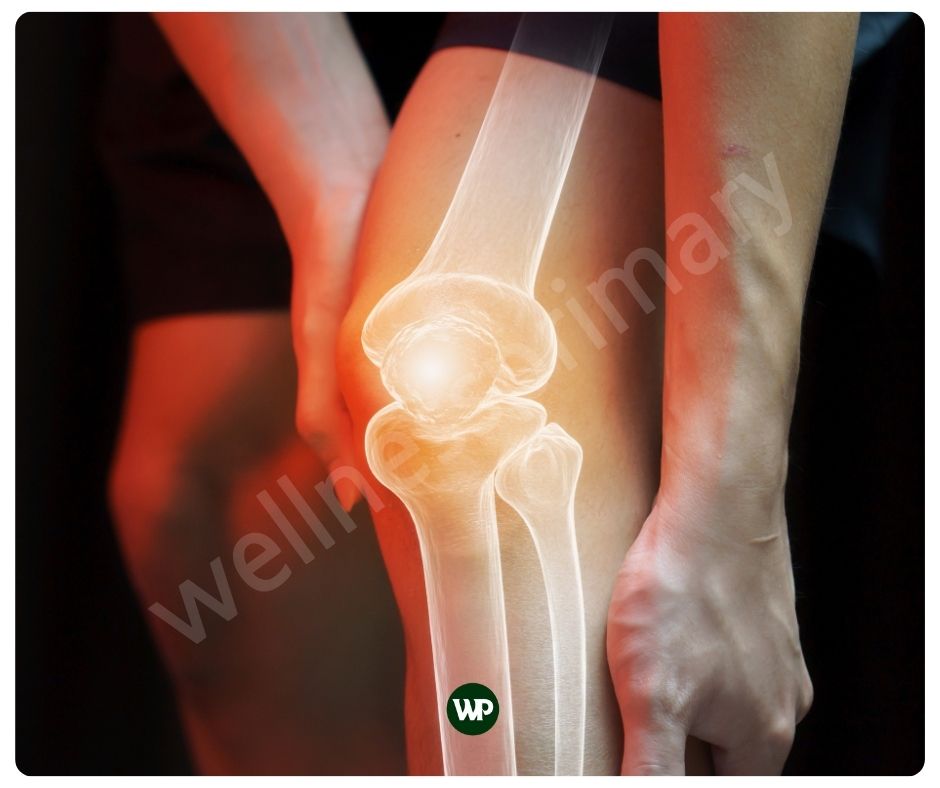

콘드로이친은 연골 조직에 존재하는 물질인데요. 주로 관절과 뼈의 건강에 중요한 역할을 합니다. 콘드로이친은 연골 내에 존재하는 중요한 글리코사미노글리칸의 일종으로, 주로 연골, 뼈, 힘줄, 인대 등에 많이 있습니다. 연골의 주요 구성 요소인 콘드로이친은, 관절의 부드러운 움직임을 도와주며 충격을 흡수해 통증을 완화해 줍니다. 또한 당과 단백질의 복합체인 프로테오글리칸의 일부로, 연골의 탄력성을 높이는데에도 도움이 됩니다. 주로 상어와 소의 연골에서 추출하여 영양제로 섭취할 수 있습니다.

연골은 관절의 움직임을 부드럽게 하고 충격을 흡수하는 역할을 하는데요. 이러한 연골의 역할은 관절이 원활하게 움직이는데 중요하지요. 콘드로이친 효능은 위에서도 언급하였 듯이 연골 조직에 존재하며 연골 내부의 구조를 강화하고 유지하는 데 도움을 주어 관절 건강에 도움을 줍니다. 또한 콘드로이친은 관절의 윤활을 증진시켜, 움직임 시 마찰과 통증을 줄여주어 관절이 부드럽게 움직일 수 있도록 도와줄 수 있습니다.

인간의 연골의 두께는 무릎의 대퇴골 연골의 경우 약 3mm에서 4mm 정도로 가장 두껍습니다. 어깨 관절 연골은 약 1mm~2mm에 불과하지요. 연골은 우리의 움직임을 위해 매우 중요한 역할을 하지만 실제로 매우 얇습니다. 그래서 가능한 빨리 연골 보호에 신경을 써야 합니다. 콘드로이친 효능은 연골의 손상을 예방하며, 이는 특히 연령 증가에 따른 연골 퇴화를 막는 데 중요한 역할을 합니다. 콘드로이친은 이미 손상된 연골의 경우, 그 회복을 돕고, 연골 세포의 재생을 촉진하는 매우 중요한 역할을 합니다.

관절염과 같은 염증은 연골을 파괴할 수 있는데요. 콘드로이친은 염증을 유발하는 화학물질의 생성을 억제하며, 이로 인해 관절염과 같은 염증성 질환에서 발생하는 통증과 부기를 감소시켜 줄 뿐 아니라 연골의 파괴도 막아줄 수 있습니다. 또한 염증이 감소함으로써 관절 통증을 완화하는 데 도움을 줍니다.